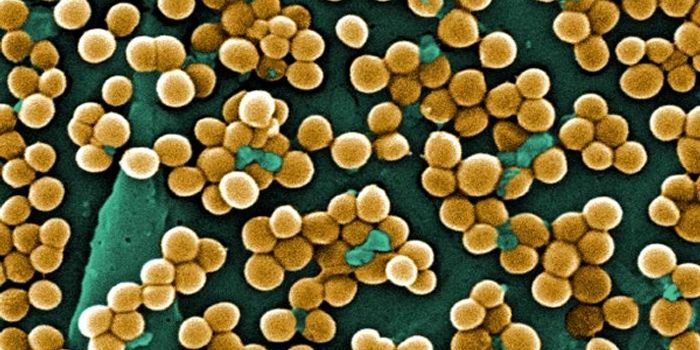

JUN 08, 2018MicrobiologyThe S. aureus pathogen doesn't only invade bone, it uses it as a snack.

AUG 20, 2016Clinical & Molecular DXCan the staph superbug, also known as MRSA, be brought down by salt? Scientists finally expose a key weakness in these b ...

MAR 11, 2015MicrobiologyHouseholds can serve as a reservoir for transmitting methicillin-resistant Staphylococcus aureus (MRSA), according to a ...